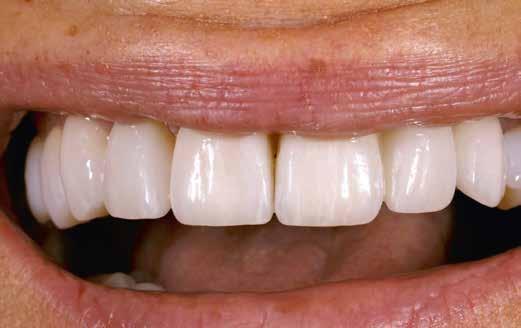

A CAD/CAM elterjedése ellenére az analóg eljárások nem szűntek meg funkcionálni. Esetbemutatásunk demonstrálja, hogyan rehabilitáltunk sikeresen az esztétikus zónában jól bevált munkamenettel, de új préskerámia recepttel. Az eredmény: természetes transzlucencia, opaleszcencia, fluoreszcencia – és egy boldog páciens.

Az esztétikus zóna a teljes adhezív ragasztás után abszolút természetes hatású.

Behelyezés és összefoglalás

A klinikai próba során a hölgy mégis a központi diasztéma teljes zárását kérte, amit korrektúrégetéssel valósítottunk meg. A folysavazást és szilanizálást követően a kilenc héj és a korona adhezív módon, kompozittal került rögzítésre. A régi, jól bevált analóg módszer az új VITA AMBRIA receptnek köszönhetően hatékonyan valósította meg préskerámiával az esztétikus zóna rehabilitációját. A préskerámia természetes transzlucenciája, opaleszcenciája és fluoreszcenciája élő bázist adott az egyéniesítéshez és karakterizáláshoz. A préselés utáni minimális reakciós réteg gyors kibontást és kidolgozást tett lehetővé. A préskerámia robusztussága biztonságot hozott. Az optikai összhatás és összjáték a VITA LUMEX AC leplezőkerámiával hatékonyan segítette a páciensre jellemző finomságok megjelenítését. A hölgy nagyon elégedett volt új mosolyával.